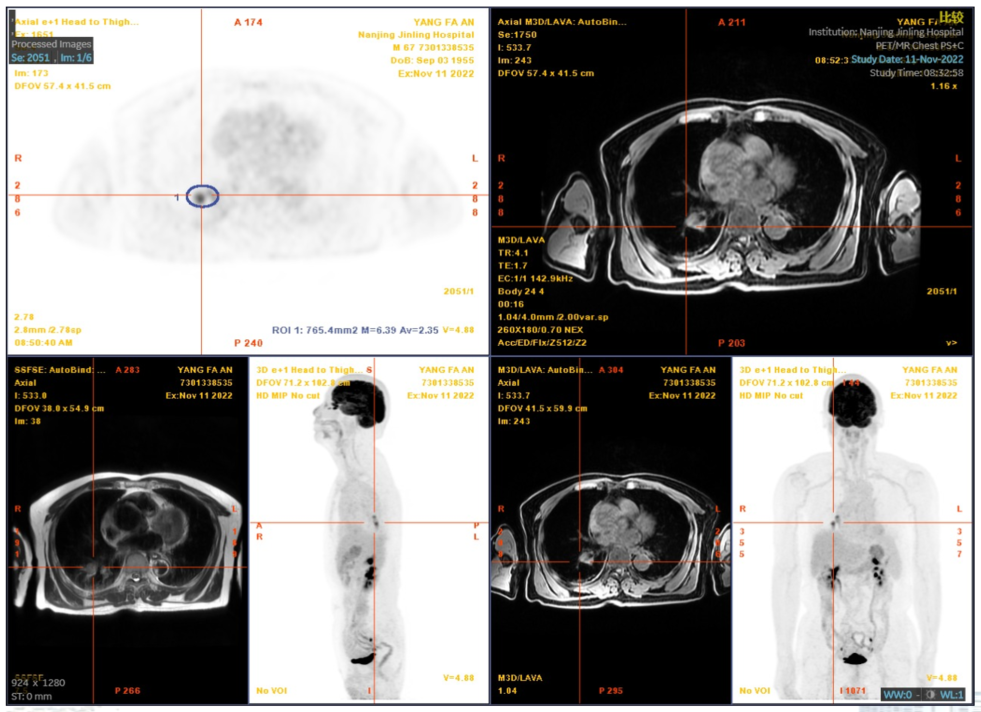

2022-05-20PET/MRI示:

1. 右肺下叶肿块(大小约62mm×41mm)及右肺门肿大淋巴结,代谢明显增高,结合病史考虑右肺下叶肺癌并右肺门淋巴结转移:右侧锁骨上区、两肺门及纵隔内淋巴结多发大小不等淋巴结,代谢轻度增高,转移不除外:

2. 右肺上叶胸膜下结节,代谢轻中度增高,转移待排;

3. 右侧局部胸膜少许结节样增厚,并少许强化,胸膜转移待排;

4. TNM分期考虑为 T4N1?M1?

5. 右侧胸腔积液,局部包裹,并右肺下叶部分萎陷:两肺下叶胸膜下间质性炎症。

图1.PET/MRI